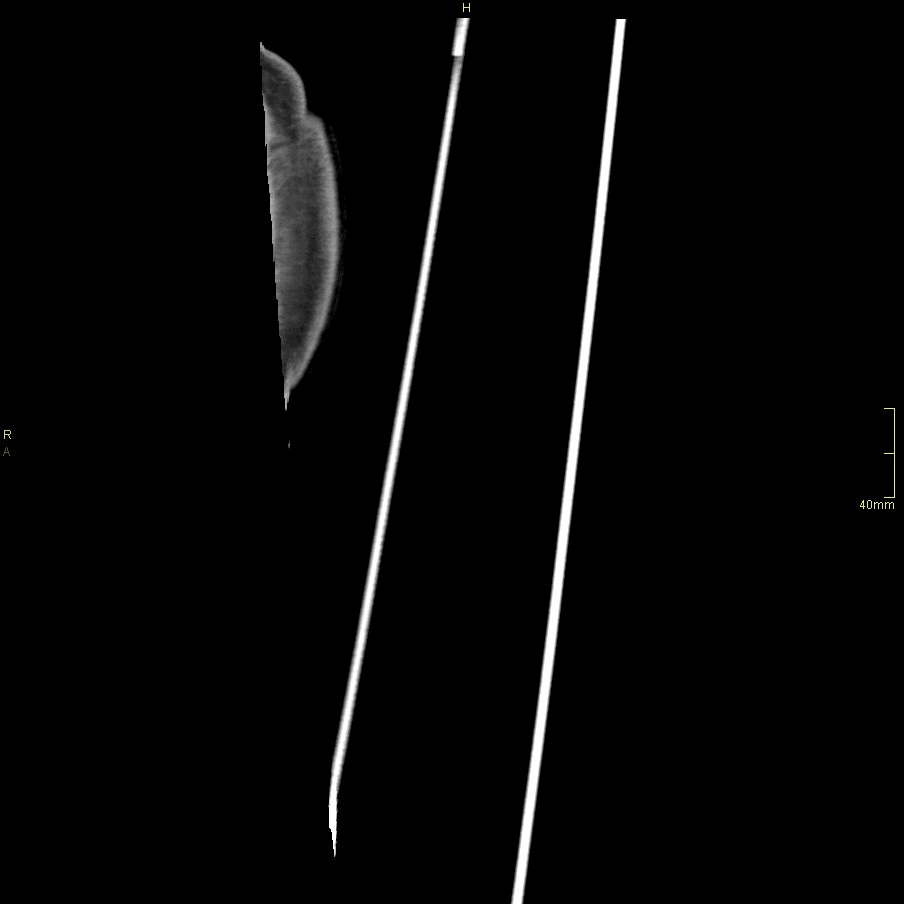

CT Humerus Contrast- Soft tissue window (coronal)

CT Humerus Contrast- Bone window (coronal)